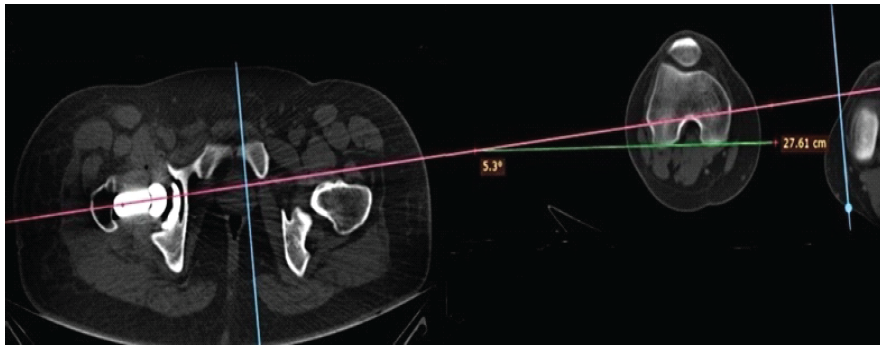

Anteroposterior pelvis and cross-table lateral hip radiographs were obtained on the 2nd post-operative day, along with a CT-scan (from L4 vertebra to distal femoral condyles). Acetabular anteversion, inclination, and femoral anteversion were measured on CT images using standardized radiological techniques by two qualified surgeons who were not part of the operating team [13,22] (Figs. 3 and 4). CA was calculated using Widmer’s formula: CA = acetabular anteversion + 0.7 × femoral anteversion [7]. Measurements from the contralateral native hip served as anatomical reference values.

Figure 4: Computed tomography measurement of femoral anteversion.